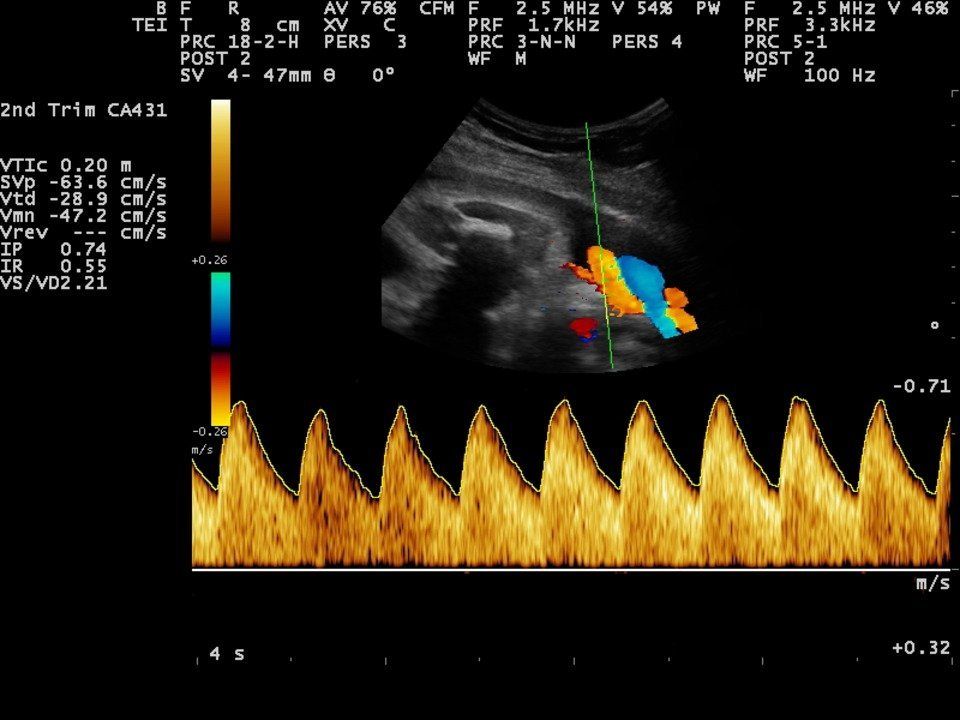

- Artera ombilicală Măsurarea Doppler.

- Măsurarea Doppler a Arterei Cerebrale Centrale.